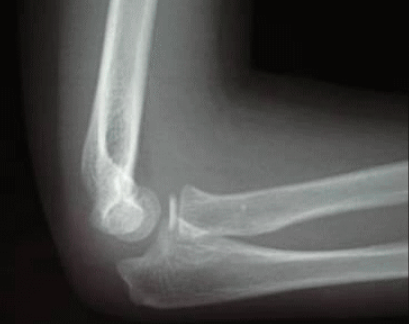

お子さんが腕を引っ張られた後に肘の痛みを生じ、腕を動かさなくなることがあります。そのような病気を肘内障と言います。幼稚園のお子さんに多く、腕が引っ張られることで、肘の輪状靭帯が亜脱臼することで生じる病気です。

圧痛や腫れ、痛みの場所を確認します。まれに骨折が隠れていることもあるため、念のためレントゲンで骨折がないかをチェックします。

徒手整復を行い治します。具体的には肘を45度屈曲にした状態で前腕を回内させて整復します。整復する際にクリックを感じたら整復されていることが多いです。それでもダメな場合は回外法を試し、シーネ固定を行い、翌日受診してもらいます。